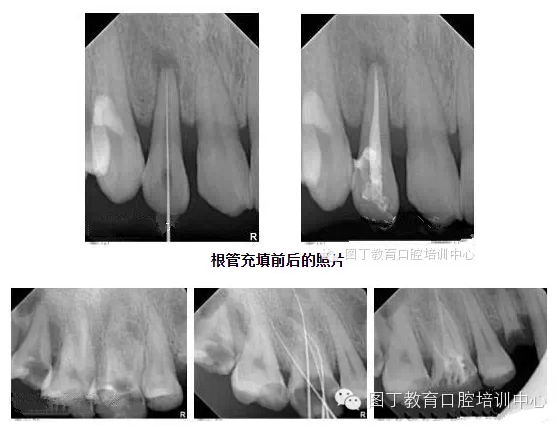

4、關于根管充填

總結(jié)幾個要點:

1,根管充填到位的前提是根管要預備好;

2,把握好充填長度;

3,選擇合適的主膠尖意義很大——合適的主尖其尖端恰好封閉根尖孔;

4,糊劑適量即可,因為充填的主體是牙膠。

5,側(cè)方加壓后的垂直加壓不可忽視,因為通過垂直加壓后的充填體更嚴實。

QQ圖片20150729094718.png